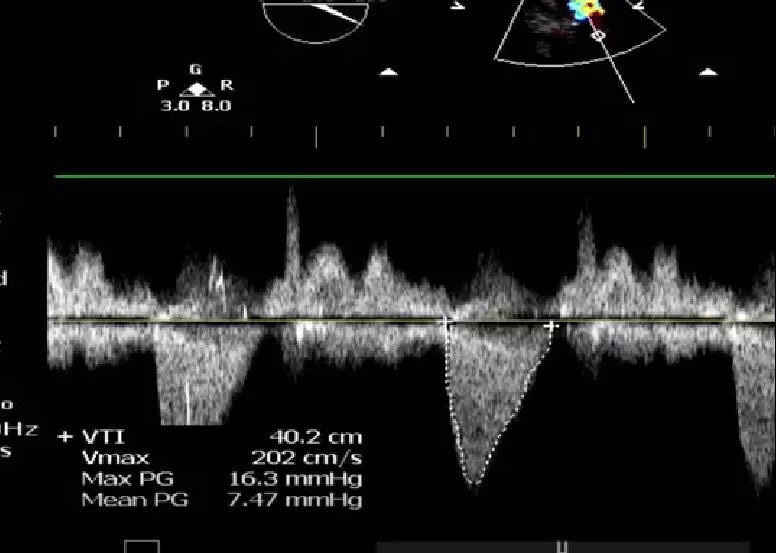

9月27日上午10时,直播开始,魏来教授团队耗时约1小时,经右侧股动脉植入23# Renatus介入主动脉瓣。瓣膜植入位置理想,功能表现出色,造影及经食道超声观察显示瓣膜无中央性返流,轻微瓣周漏,无冠脉血流受阻,无传导阻滞,主动脉瓣峰值流速降至2.0m/s,平均跨瓣压差降至7mm/Hg。手术取得圆满成功。

术前心脏彩超                               术后心脏彩超